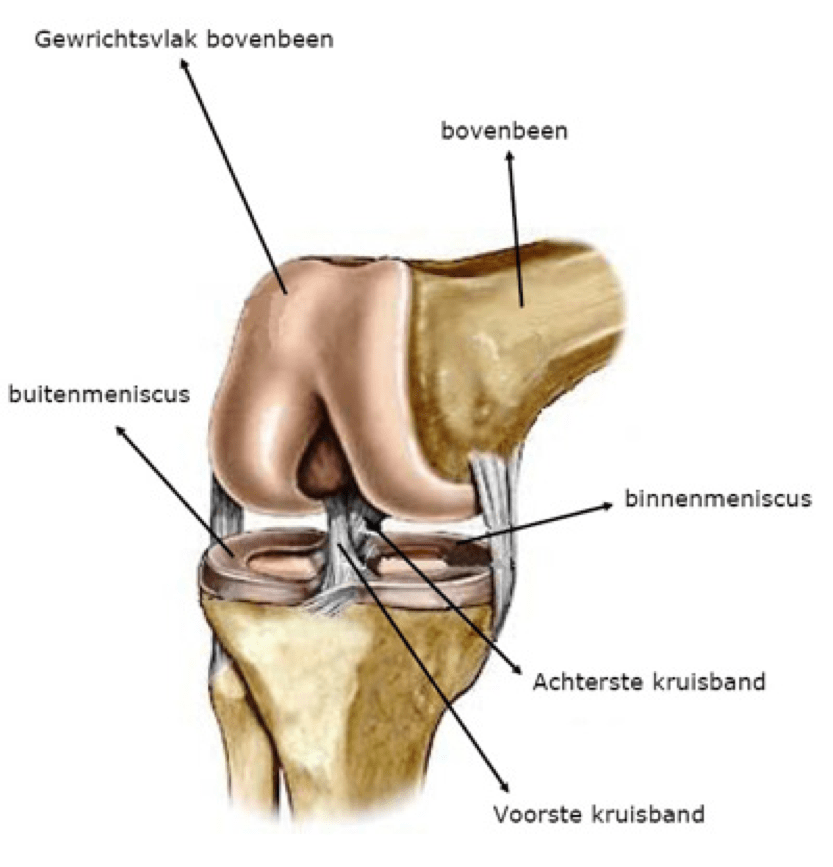

Om u te laten begrijpen wat een TKP is, willen we uitleggen hoe de anatomie van een gezond kniegewricht eruitziet.

Het kniegewricht wordt gevormd tussen het boven- of dijbeen (Lat. femur) en het scheenbeen (Lat. tibia). Zowel het bovenbeenuiteinde als het draagvlak van het onderbeen (tibia plateau) zijn bekleed met kraakbeen. Daarnaast maakt ook de knieschijf (Lat. patella) deel uit van het kniegewricht en is achteraan met kraakbeen bekleed. De knieschijf vormt het centrum van het strekapparaat van de knie en de voorzijde van het scharniergewricht. Het kniegewricht heeft drie compartimenten:

Het gewricht wordt verder gestabiliseerd door meerdere ligamenten (gewrichtsbanden) en beide menisci die ook als schokdemper werken in een natuurlijke, gezonde knie. De dijspieren geven verdere stabiliteit en kracht rond de knie. De mobiliteit van een gezonde knie bedraagt +/- 130° in diepe buiging (flexie) en bereikt een volledige strekking (extensie). Enige rotatiebeweging is in beperkte mate aanwezig.